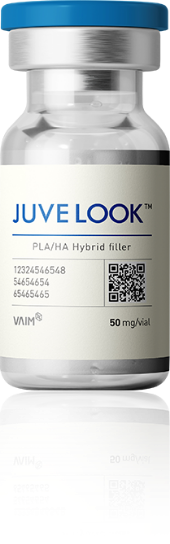

[자가 콜라겐] 쥬베룩

WHAT IS IT? - 쥬베룩은 고분자 PLA와 인체 피부 조직에 존재하는 히알루론산을 결합시킨 자가 조직 재생 콜라겐 부스터입니다. 피부에 주입된 후 바로 볼륨 효과가 나타나는 다른 필러와는 달리 자가 콜라겐 생성을 촉진하여 자연스러운 볼륨을 만들어 주며 피부 탄력, 잔주름, 피부결 개선에도 효과가 있습니다.

쥬베룩은 고분자 PLA(폴리락타이드)와 HA(히알루론산)을 결합시킨

자가조직재생 콜라겐 부스터입니다.